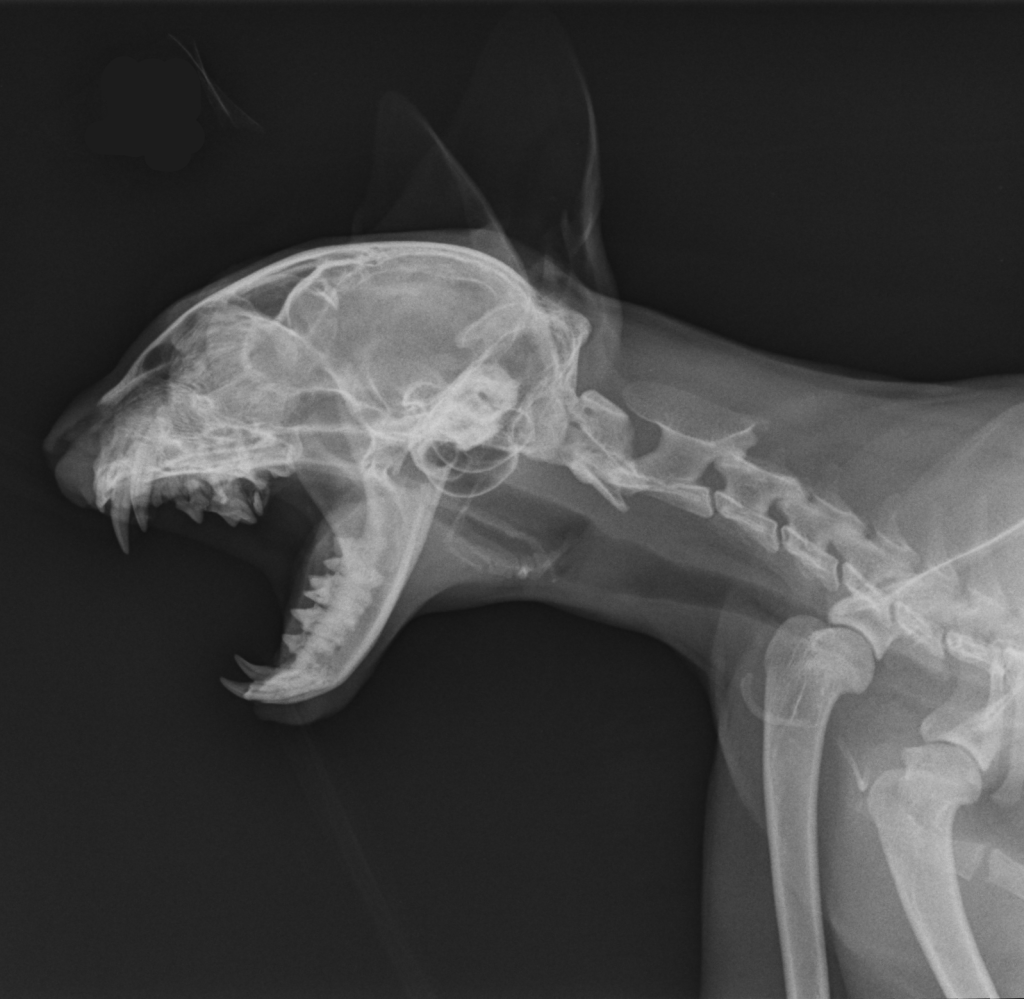

Radiographie numérique

La clinique dispose d’une salle de radiologie équipée d’un appareil de radiographie numérique. Celui-ci permet de réaliser sur place en quelques minutes les images nécessaires à l’établissement d’un diagnostic, pour l’examen des structures osseuses, et de certains organes abdominaux ou thoraciques.